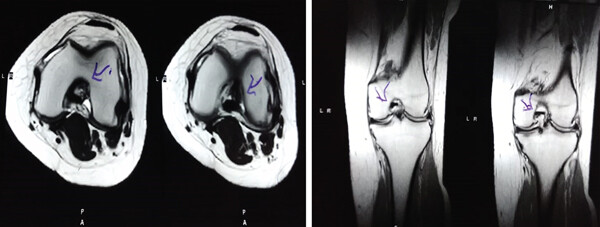

MRI檢查發(fā)現(xiàn)半月板損傷處修復(fù):3D MRI 顯示 2 年時(shí)半月板撕裂難以辨別。

移植滑膜間充質(zhì)干細(xì)胞修復(fù)前后的3D MRI圖像

結(jié)論:滑膜間充質(zhì)干細(xì)胞移植后,2年的隨訪中,患者的關(guān)節(jié)功能改善,MRI檢查發(fā)現(xiàn)半月板損傷處恢復(fù),沒有發(fā)生導(dǎo)致研究終止的重大不良事件。可以達(dá)到干細(xì)胞治療半月板損傷長(zhǎng)期療效的目標(biāo)。